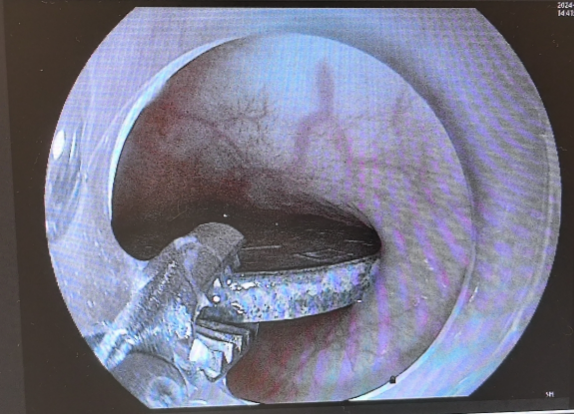

专家妙手取“金” 硬币取出时已被腐蚀发黑了

不到3分钟,王艳丽就将卡在强强胃里的硬币取了出来,整个手术过程迅速而精准。被取出来的一毛钱的硬币,直径约有1.9厘米宽,王艳丽表示,吞进异物有些对人体是有害的,特别像这种金属类的异物或者一些对消化道有潜在危害的异物,如果观察超过72小时未排除,还是建议应及时取出。术后,强强精神状态挺好,没有什么不良反应和副损伤,也能正常进食。